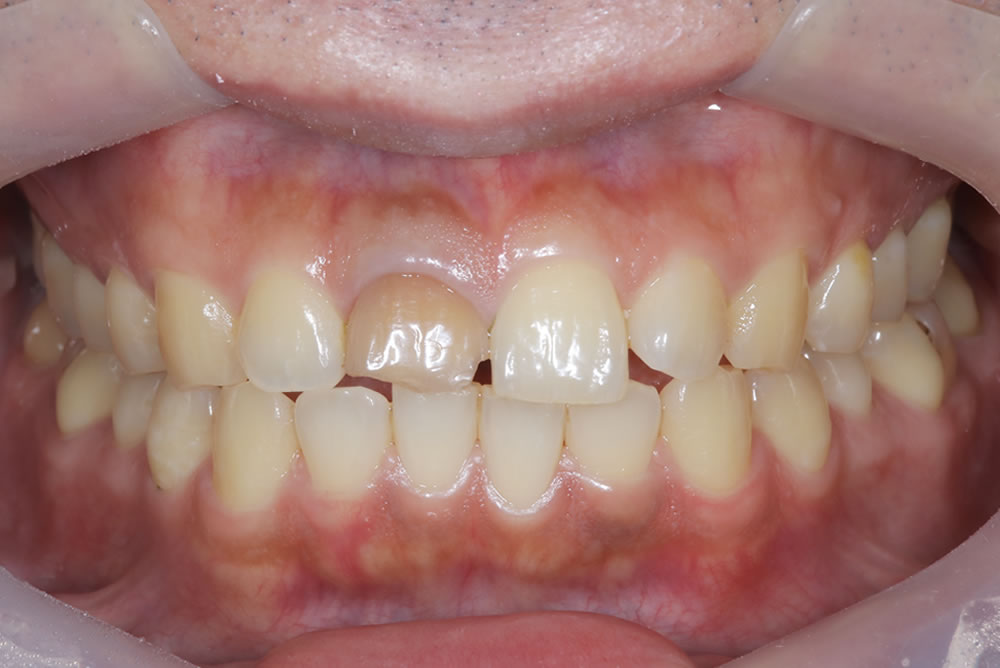

上部構造(精密な仮歯)を作成・装着

歯茎の治癒を待ち、2ヵ月後に型取りしてインプラントの上部構造(精密な仮歯)を作成・装着しました。

精密な仮歯を使用して「完成形」をすり合わせます!

インプラントに装着した精密な仮歯で経過を観察して

- 歯の長さ

- 形

- 隣の歯との調和

- 笑ったときの見え方

これらを何度も確認・微調整していきます。

この工程を丁寧に行うことで、最終的なかぶせ物の完成度は大きく変わります。